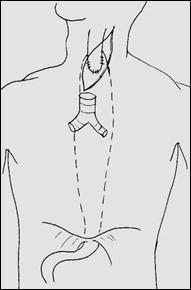

Рис. 5. Схема выкраивания трансплантата из большой кривизны желудка в антиперистальтической позиции по Гаврилиу. Выполнено обходное шунтирование стриктуры нижнегрудного отдела пищевода (вариант 1 – без резекции пищевода, вариант 2 – с резекцией рубцово измененного пищевода)

Рис 6. Схема доступов для резекции пищевода с одномоментной пластикой целым желудком при операции Льюиса и операции, схема которой изображена на рис. 5.